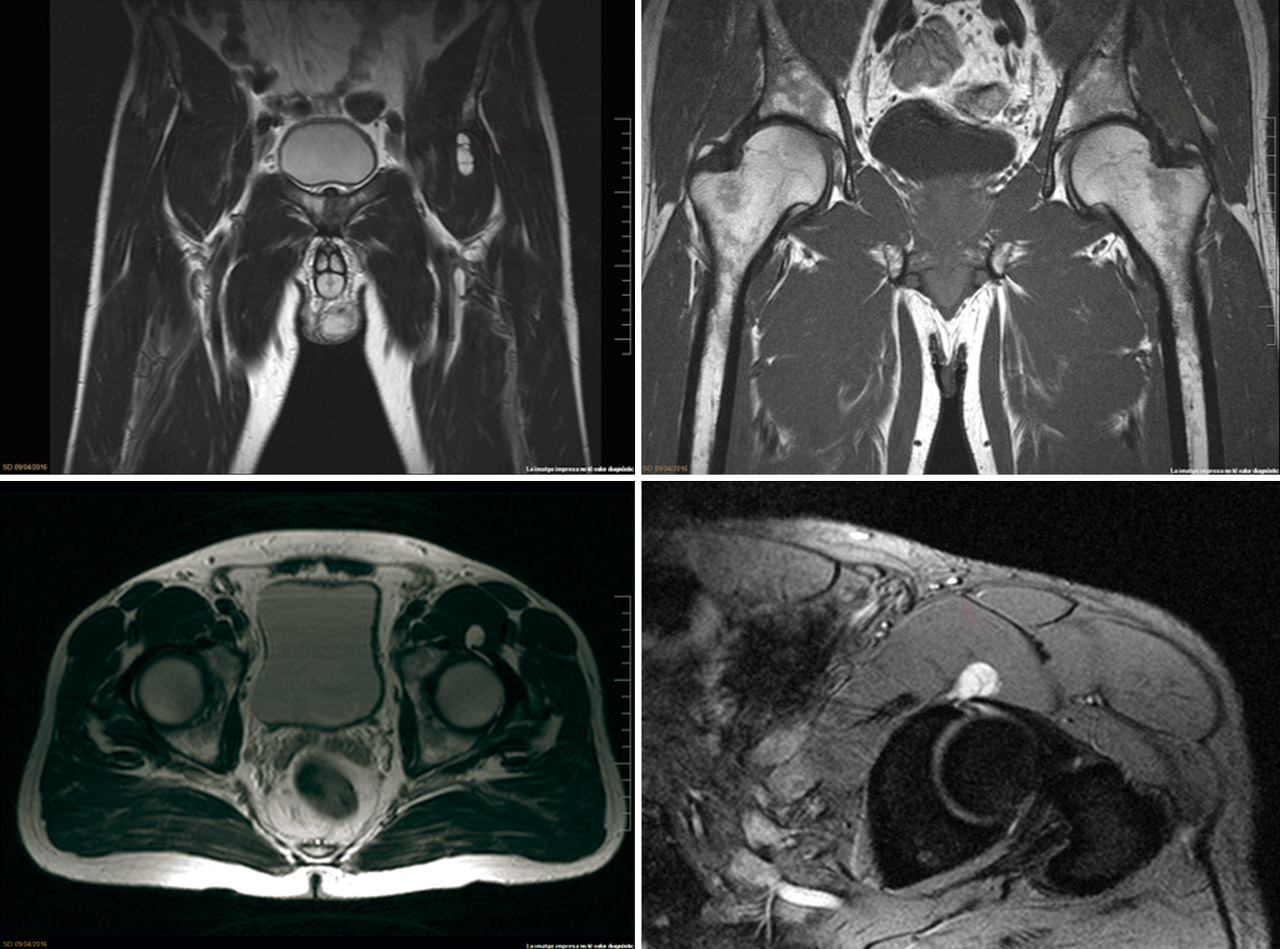

Figura 2. A: imagen coronal de STIR que muestra la lesión quística (flecha roja) que ocupa el músculo psoas; B: desgarro labral (flecha amarilla); C: imagen axial T2 que compara ambas caderas. La lesión quística (flecha roja) se identifica en el espacio articular anterior de la cadera izquierda; D: T2 imagen sagital del quiste labral (flecha roja) inferior a la espina iliaca anteroinferior.